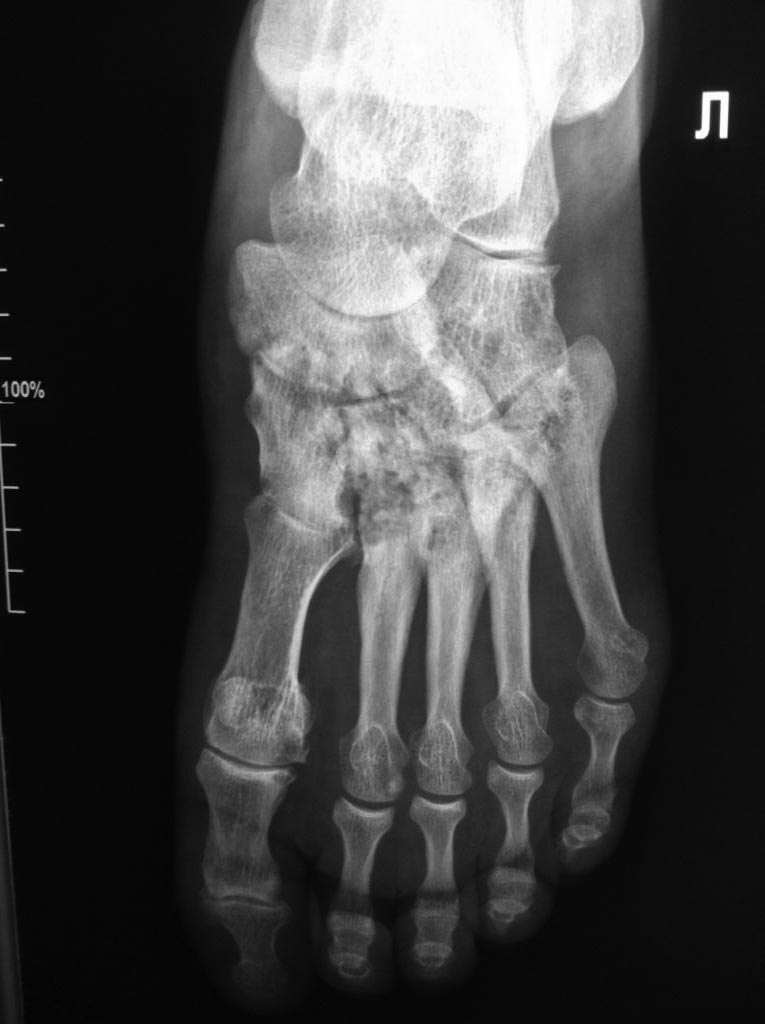

Асептический некроз костей среднего отдела стоп.

Доброго времени суток. Обратился пациент, 62 года, бытовые и трудовые условия в данное время не отягощены и не были никогда тяжелыми, без вредных привычек,

со слов оперативных вмешательств не было, курсов гормональной терапии не получал, периодически принимает лекарственные препараты от арт. гипертензии. Без видимых причин около 1 года назад появились боли в стопах при ходьбе и нагрузке, в связи с чем обратился к ортопеду.

Лаб исследования: Ревмофактор, С-реакт. белок, АЦЦП, Мочевая кислота и др. в пределах возрастной нормы. Хотелось бы услышать мнения. Заранее благодарен.

Добрый день. Похоже на Charcot

И, забыл добавить, есть мнение, что ингибиторы АПФ, например эналаприл, эту саму артропатию Шарко могут вызывать.